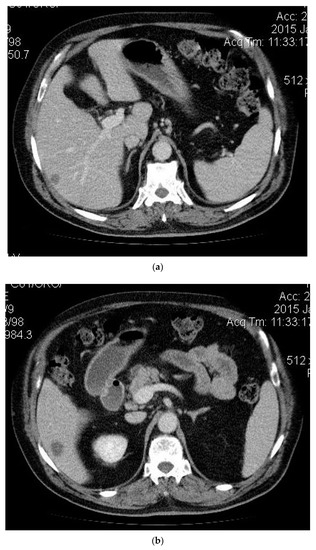

2. Case Presentation